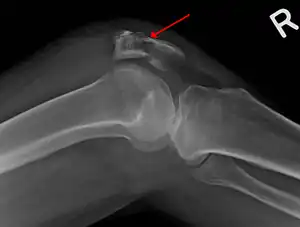

![]() | |

| A fracture of the patella seen on a lateral view | |